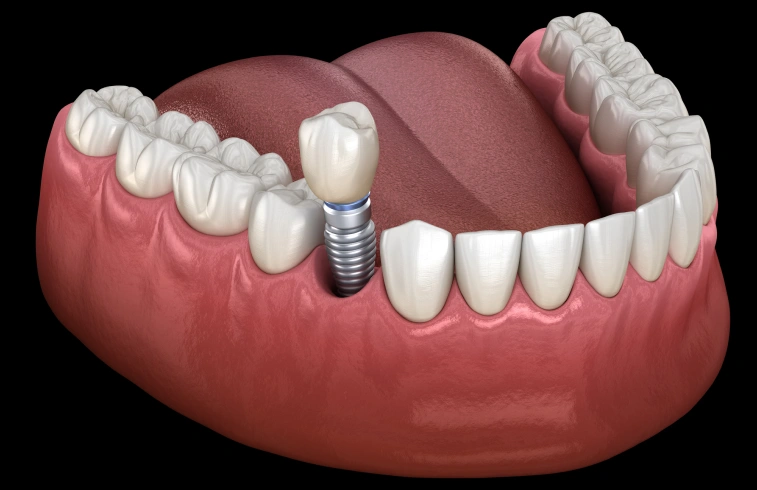

A dental implant is a small titanium post that is surgically placed into the jawbone to replace the root of a missing tooth. Over time, the implant integrates with the bone, creating a stable foundation for a custom crown, bridge, or denture.

The implant is placed into the jawbone, where it is allowed time to heal and integrate with the bone. Once healing is complete, a custom restoration is attached to the implant to complete your smile.